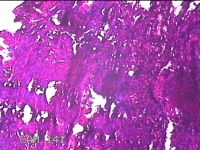

宫颈管内膜组织

性别

女

年龄

39岁

临床诊断

子宫异常出血 子宫内膜不典型增生?子宫内膜占位性病变待查 慢性宫颈炎

一般病史

阴道流血3天,增多1小时。

标本名称

大体所见

灰白暗红色不规则碎组织1.8x1.3x0.3cm一堆。

子宫颈管内膜和子宫内膜组织,没有什么大问题。